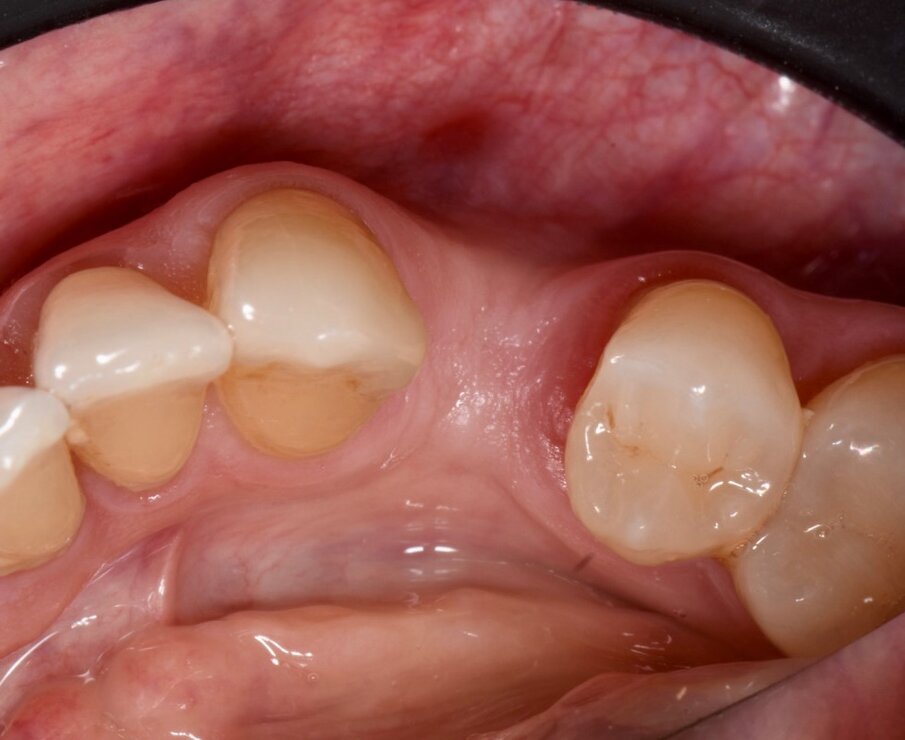

Sono stati selezionati 10 pazienti ASA 2 senza patologie sistemiche con necessità di riabilitazione in zona 44-45 o 34-35 tramite estrazione e inserimento implantare, che presentassero un volume osseo idoneo senza la necessità di GBR ma con la possibilità di aumentare i tessuti molli in modo da armonizzare il volume perimplantare a fini estetici e per il mantenimento del successo a lungo termine (Fig. 1).

Prima dell’estrazione (S0), ad ogni paziente è stata eseguita una scansione intraorale tramite scanner iTero (Align Technology) (Fig. 2), e le scansioni sono state archiviate. A distanza di 2 mesi dall’estrazione è stato creato un lembo vestibolare a busta, a mezzo spessore, è stato inserito l’impianto nel sito (Figg. 3, 4) ed è stata posizionata la matrice in collagene suino volumetricamente stabile Geistlich Fibro-Gide (Geistlich Pharma), stabilizzandola al periostio con due punti di sutura riassorbibili interni (Fig. 5)7. Il lembo è stato quindi suturato con suture non riassorbibili e punti sospesi in modo da garantire la chiusura primaria e mantenere la matrice sommersa ma non compressa (Fig. 6).